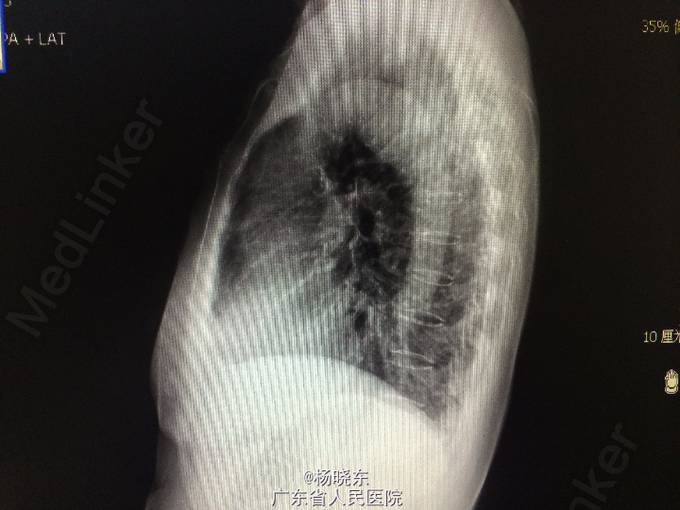

主诉:反复胸背痛1年,加重1月。 病史:患者1年前无明显诱因出现右侧胸背痛,性质为隐痛,无向周围放射。遂至当地医院门诊就诊,查胸部CT,考虑“胸膜肿瘤”,建议手术处理,但患者拒绝未予治疗,症状持续数天后自行消失。后间断出现类似症状,但均可忍耐。1月前患者自觉右上肢上抬及抬举重物时右侧胸背痛明显,不伴有其余部位牵涉痛,未予重视。近1周来,患者自觉症状加重,疼痛致右上肢不可上抬,弯腰时加重,平卧时可缓解。现为进一步手术治疗入院,无发热,无头晕、头痛,无咳嗽、咳痰,无气促、心悸,无恶心、呕吐,无腹痛、腹泻,无皮疹、无双下肢浮肿。自起病以来,精神、睡眠可,食欲可,二便正常,体重近1月下降2kg。

查体:右侧胸肋部及肩胛区压痛明显。 辅查:胸片,CT。

诊断:胸膜间皮瘤 处理:右侧胸膜肿瘤切除术